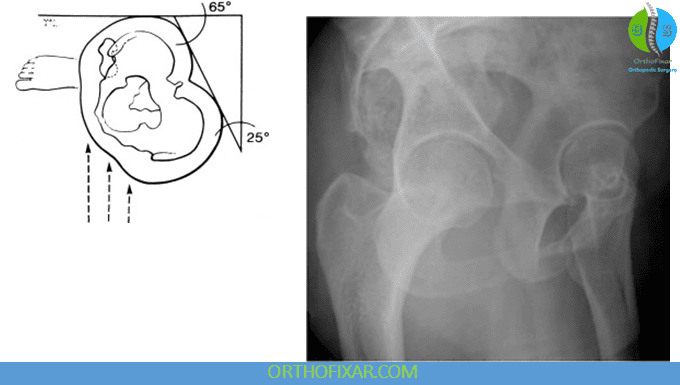

False-Profile Hip X-Ray

The false-profile view is an oblique (65°) standing radiograph used to assess anterior acetabular coverage of the femoral head. It is the standard view for calculating the anterior center-edge (CE) angle.

Measurement steps:

- A vertical line is drawn through the center of the femoral head.

- A second line is drawn from the most anterior point of the acetabular sourcil (“eyebrow”) to the femoral head center.

- The angle between these two lines is the anterior CE angle.

Interpretation:

- < 20° → structural instability of the hip

- Normal → typically > 20°

This measurement is particularly important when evaluating dysplasia, instability, or pre-arthritic structural abnormalities in young adults.